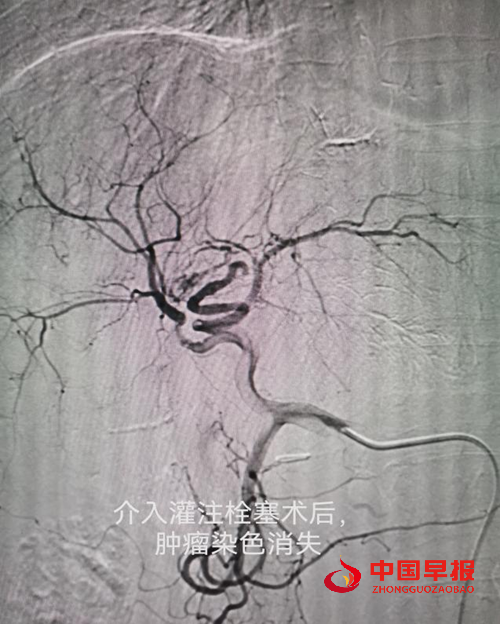

病例一:刘先生,男,55岁,患肺癌,经过三次介入微创手术+三次细胞治疗+靶向治疗,肺癌缩小90%,全身脊柱转移灶得到控制硬化,全身剧痛消失,处于NED状态。